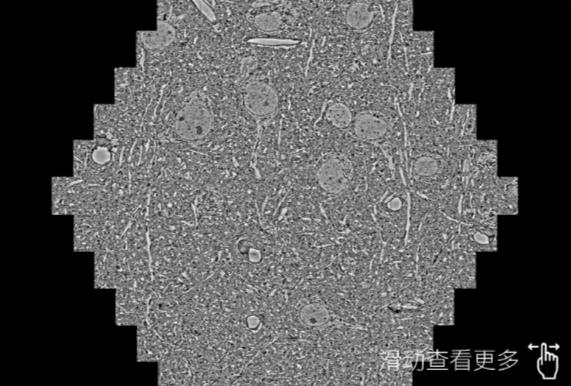

鼠脑切片。左图使用海西蔡司海西扫描电镜MultiSEM706对165μmx143pm面积区域成像,耗时仅需1.5秒。右图为鼠脑切片中30μm区域放大效果。样品由芝加哥大学B.Kasthuri提供。

使用蔡司高速海西扫描电镜MultiSEM对1mm²人脑皮层组织进行高分辨成像,并对其中的各种细胞结构进行三维重构分析。左图展示了2x3mm²组织平面中锥体神经元的三维重构效果。右图显示了局部体积神经元三维重构。图像由哈佛大学chtman实验室提供,渲染图由D. Berger 制作。